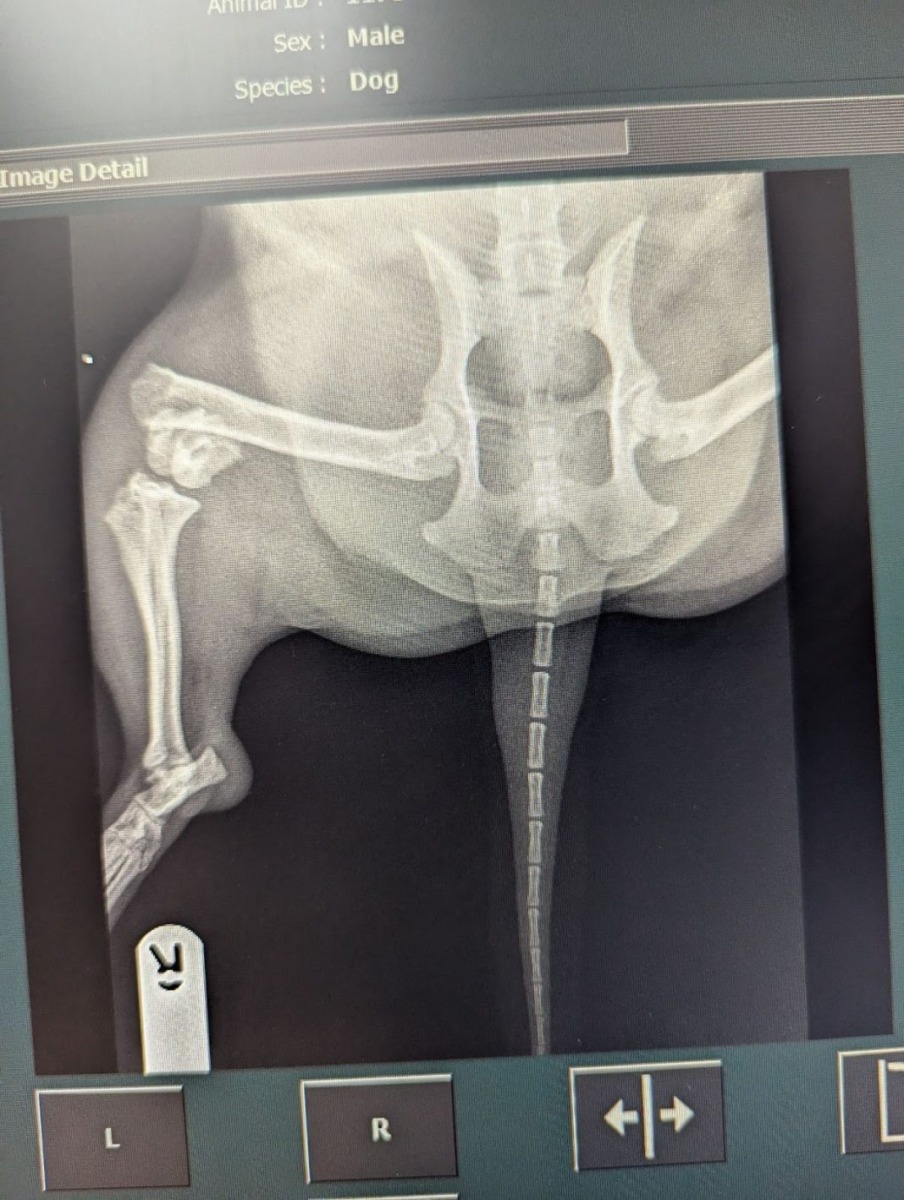

Cazul a ieșit la iveală în iulie 2024, când un terrier Jack Russell, în vârstă de șase ani, a fost dus la o clinică veterinară cu o fractură de picior. Medicii au constatat că rana era cauzată de un traumatism sever, ridicând suspiciuni privind modul în care a fost produsă, potrivit Dog Today.

Investigațiile ulterioare au scos la iveală și alte leziuni, inclusiv traumatisme la cap și vânătăi abdominale, care nu corespundeau explicațiilor oferite de proprietară. Medicii au descoperit și un istoric inexplicabil de răni anterioare.

radiografia unui câine

sursa foto: Dogs Today Magazine

Ofițerii pentru protecția animalelor, împreună cu poliția, au intervenit și au preluat câinele, care a fost transportat pentru tratament într-un centru specializat. Ancheta a arătat că mediul în care trăia animalul nu prezenta pericole care ar fi putut cauza accidental astfel de răni, ceea ce a dus la concluzia că animalul era abuzat.